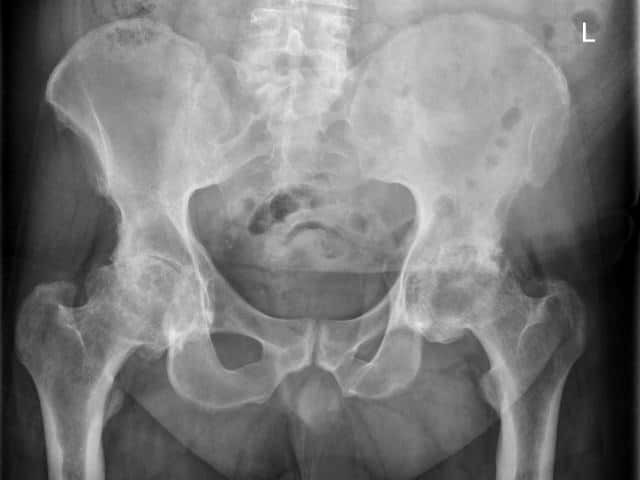

X-ray findings that are characteristic of psoriatic arthritis include:

AP Pelvis